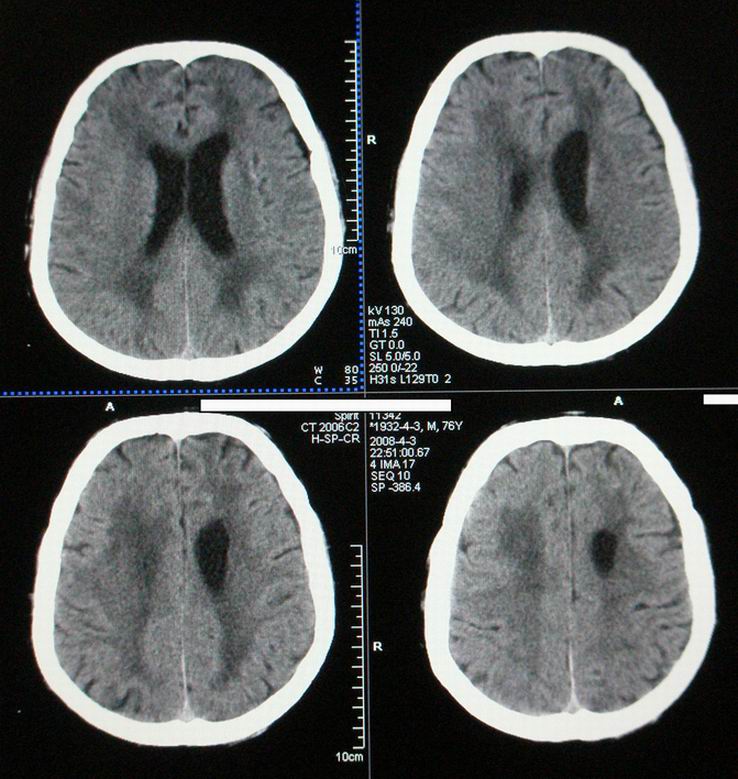

以下是引用随光逐影在2008-4-5 7:46:00的发言:[br]1)考虑为:多发性脑转移瘤。建议:行进一步检查。2)多发性腔隙性脑梗塞。3)脑白质病。4)脑萎缩。

以下是引用zjzjr在2008-4-5 9:00:00的发言:[br]1.双侧颞叶占位性病变,考虑为转移瘤可能性大。[br]2.左侧基底节区陈旧性腔隙性脑梗塞。[br]3.脑白质病。建议mri进一步检查。

以下是引用xuhuihong在2008-4-5 0:59:00的发言:[br]1.双侧颞叶占位性病变,考虑为转移瘤可能性大。[br]2.左侧基底节区陈旧性腔隙性脑梗塞。[br]3.脑白质病。建议mri进一步检查。

以下是引用形影不离在2008-4-4 23:29:00的发言:[br]1.双侧颞叶占位性病变,考虑为转移瘤可能性大。[br]2.左侧基底节区陈旧性腔隙性脑梗塞。[br]3.脑白质病。